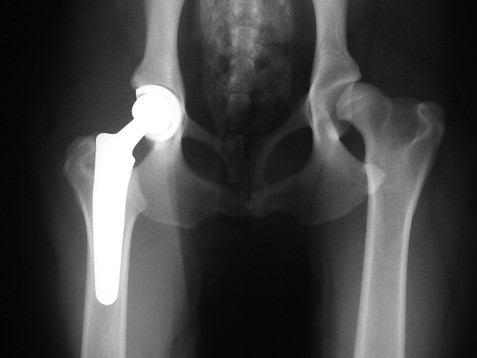

Willows is very happy to announce that we now have an expert team of five Orthopaedic Surgeons who are certified to carry out the complex Total Hip Replacement (THR) operation.

The Orthopaedic Team is able to perform total hip replacements on all patients from the smallest dog or cat, weighing only a couple of kilos, right up to the largest dogs weighing more than 100kg.